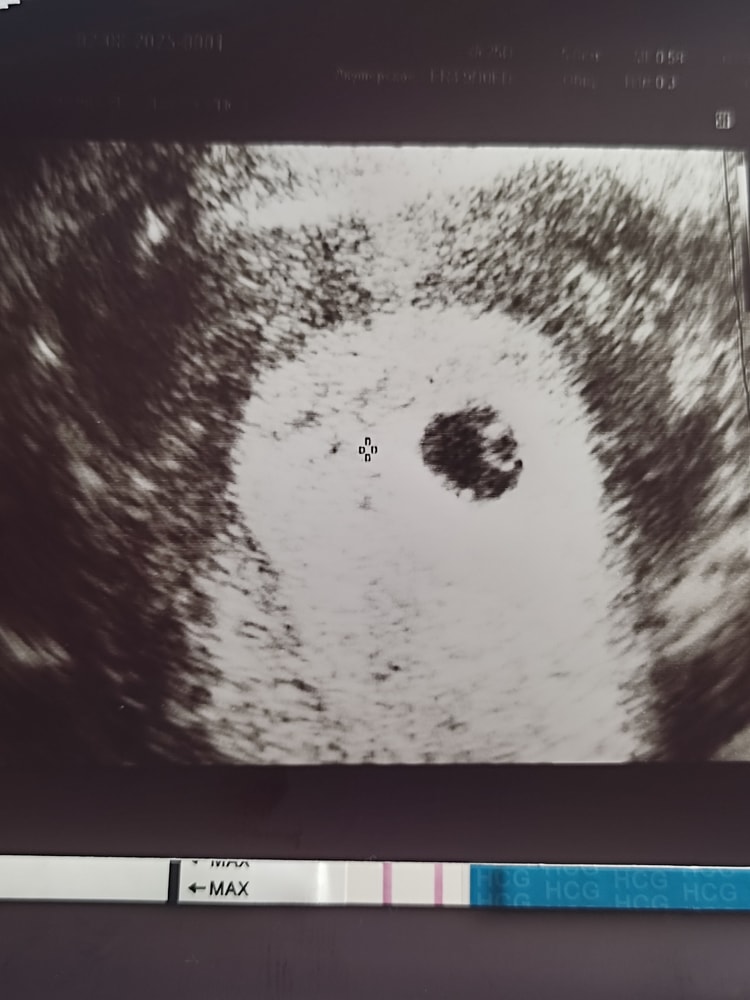

Добрейшее утречко! Официальное УЗИ назначено на 25 дпп, но естественно я не выдержала и отправилась сегодня искать ПЯ.

ПЯ в матке, внутренний диаметр 7,5 мм, ЖМ 2,5 мм. Эмбриончика пока не видно, но я и не рассчитывала. Все хорошо) Заключение: беременность 5-6 недель. По месячным 5+2!

Ура!!! Расти, наша крошечка, мы очень любим тебя и ждём!